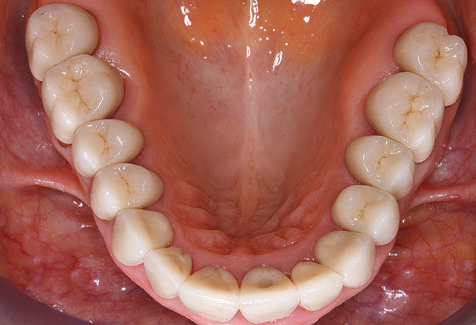

A 52-year-old patient presented in our clinic for the first time in 2004 following tooth loss in the third quadrant, expressing a desire for a new prosthetic restoration. Periodontal and radiological diagnostics revealed the need for extensive periodontological treatment. In addition, teeth 48, 28 and 27 were attributed a very poor prognosis and were subsequently extracted (Fig. 1). Following the successfully completed, systematic periodontological treatment, a fixed dental implant was inserted with the introduction of five implants in tooth regions 35, 36, 37, 46 and 47. Prosthetic treatment of the natural teeth was effected with veneered zirconium dioxide ceramic crowns; the implants were composed of two-piece, individual zirconium dioxide abutments and similarly veneered crowns made of a zirconium dioxide ceramic (Cercon base colored, Dentsply Sirona Lab). Definitive insertion of the prosthetic restoration occurred in 2005.